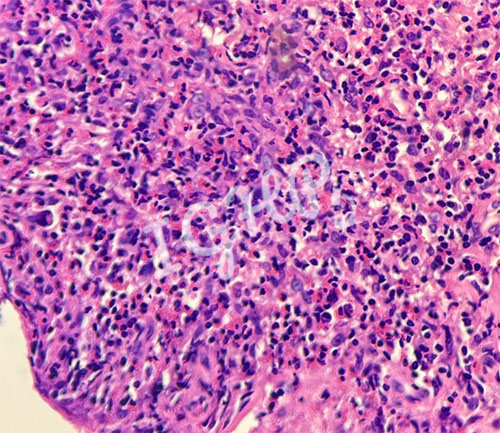

Microscopic Images-

HL is rarely associated with necrotising granuloma seenin around 1.8% cases.The Hodgkins cells are usually negative on CD45 IHC with rosetting by CD3 cells and perinuclear dot positivity on CD30 IHC and variably for CD15. The possible pathogenesis includes T cell mediated immune response against the tumor cells, tumor antigen stimulation causing fibrosis followed by granuloma formation.